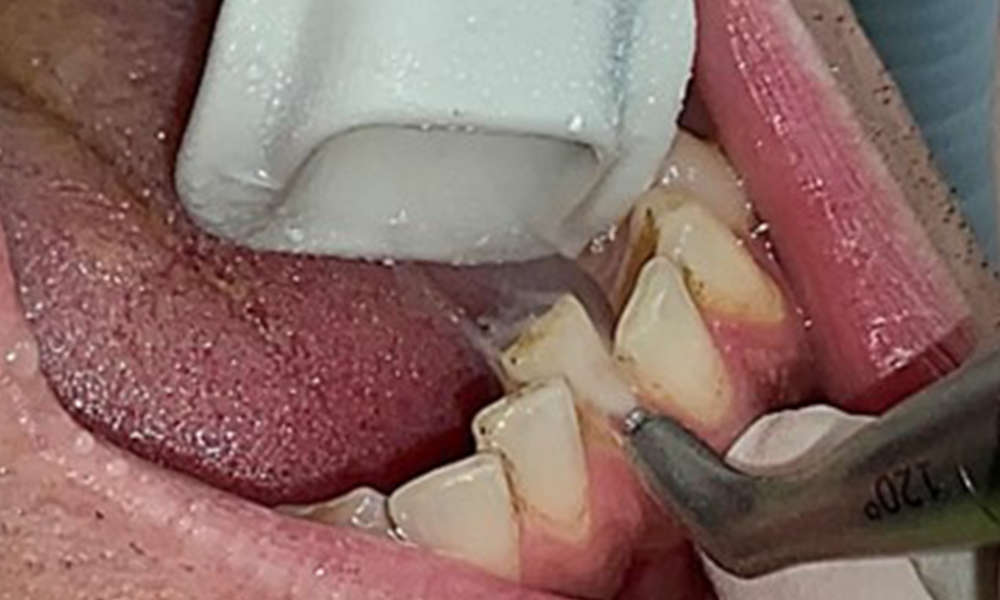

Nahaufnahme der Zähne

Abb. 5: Nahaufnahme der Zähne 45-47. Grüne Pfeile zeigen Attritionen und Erosionen im Bereich der bukkalen Höcker mit partiellem Schmelzverlust, © Dr. R. Krapf

Dental zeigt sich ein vollbezahntes Gebiss mit 28 Zähnen. Auffällig sind Erosionen und Attritionen

(Abb. 4, Abb. 5). Der Patient trägt seit vielen Jahren nachts eine Schiene mit adjustiertem Aufbiss aufgrund Bruxismus. Die Erosionen sind auf den langjährigen Konsum isotonischer Getränke zurückzuführen. Parodontaler Knochenverlust und aktive kariöse Läsionen sind nicht vorhanden.